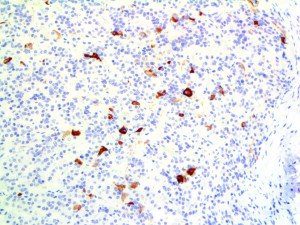

It is the ICU physician who is most likely to witness one of the deadliest manifestations of the abnormal immunological response, the cytokine storm syndrome (CSS). This response is also referred to by some as the cytokine release syndrome (CRS). CSS is characterized by continuous activation and expansion of macrophage and lymphocyte populations, which secrete large amounts of cytokines, causing the cytokine storm. This massive cytokine release is akin to hemophagocytic lymphohistiocytosis (HLH) disease, a syndrome characterized by initial unchecked and persistent activation of cytotoxic T lymphocytes and NK cells.

Clinical and laboratory manifestations of HLH include fever, enlarged liver and/or spleen, neurologic dysfunction, coagulopathy, liver dysfunction, cytopenias (i.e., low levels of erythrocytes, leukocytes, and/or platelets), hypertriglyceridemia, hyperferritinemia, hemophagocytosis, and eventually diminished NK cell activity as the immune system becomes progressively paralyzed. HLH can be familial (primary HLH) or secondary to another disease process (sHLH), such as rheumatic disease, in which it is referred to as macrophage activation syndrome (MAS, characterized by elevated ferritin).